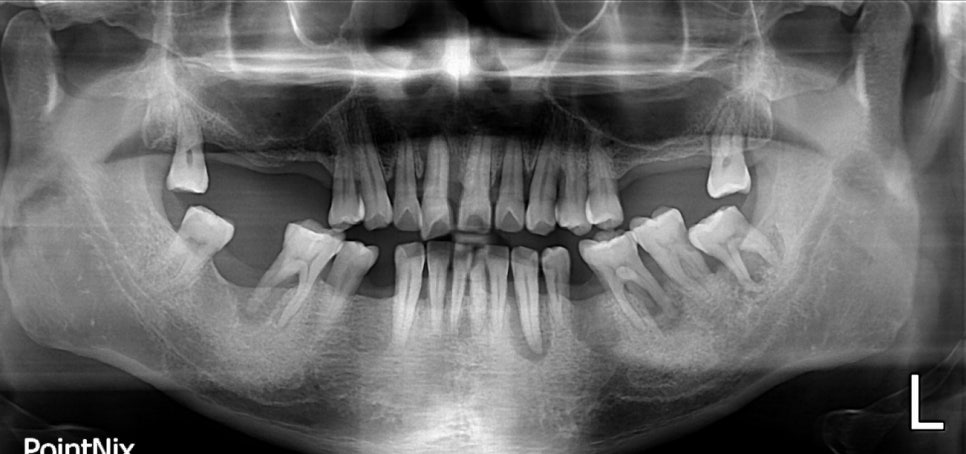

당뇨병 환자로 치주염을 앓고 있을 때의 X-RAY

당뇨질환을 가지고 계신 분 중 치주염을 앓고 계신 경우가 상당히 많습니다. 이러한 원인은 당뇨로 인해 면역기능이 약화되어 세균 감염의 위험이 일반 경우보다 높습니다. 당뇨병의 여러 합병증 중에 잇몸병은 6번째 정도 흔한 합병증이며,

특히 혈당이 조절되지 않을 경우에는 잇몸병의 진행이 매우 빨라져 위험합니다.